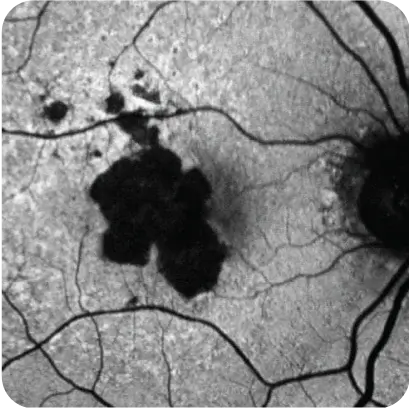

What may be happening to the retina and your patient's vision7

What may be happening to the retina

What may be happening to your patient's vision7

Loss of peripheral, low‑light vision

Representation of vision loss for illustrative purposes only.

Images courtesy of Heidelberg Engineering, Dr. Julie Rodman, and Dr. Mohammad Rafieetary.